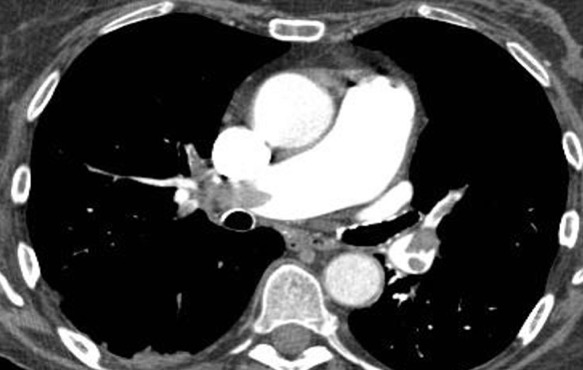

CT pulmonary angiography shows significant partial filling defects involving the right and left pulmonary artery with extension to its lobar branches. Main pulmonary artery to aorta ratio is increased (greater than 1).

Case courtesy of Dr Jeremy Jones, <ahref=”https://radiopaedia.org/”>Radiopaedia.org</a>. From the case <a href=”https://radiopaedia.org/cases/13211″>rID: 13211</a>

The other imaging findings to be mentioned (as they indicate prognosis) are:

- Thrombus burden (subjective)

- Right ventricle: Left ventricle ratio (normal<0.9)

- Changes in bilateral lungs (infarcts)

- Contrast reflux into IVC (due to high pressure in the right atrium).

The most important poor prognostic indicator is increased RV/LV ratio which is a sign RV strain.

Case courtesy of Dr Charlie Chia-Tsong Hsu <ahref=”https://radiopaedia.org/”>Radiopaedia.org</a>. From the case <a href=”https://radiopaedia.org/cases/31363″>rID: 31363</a>